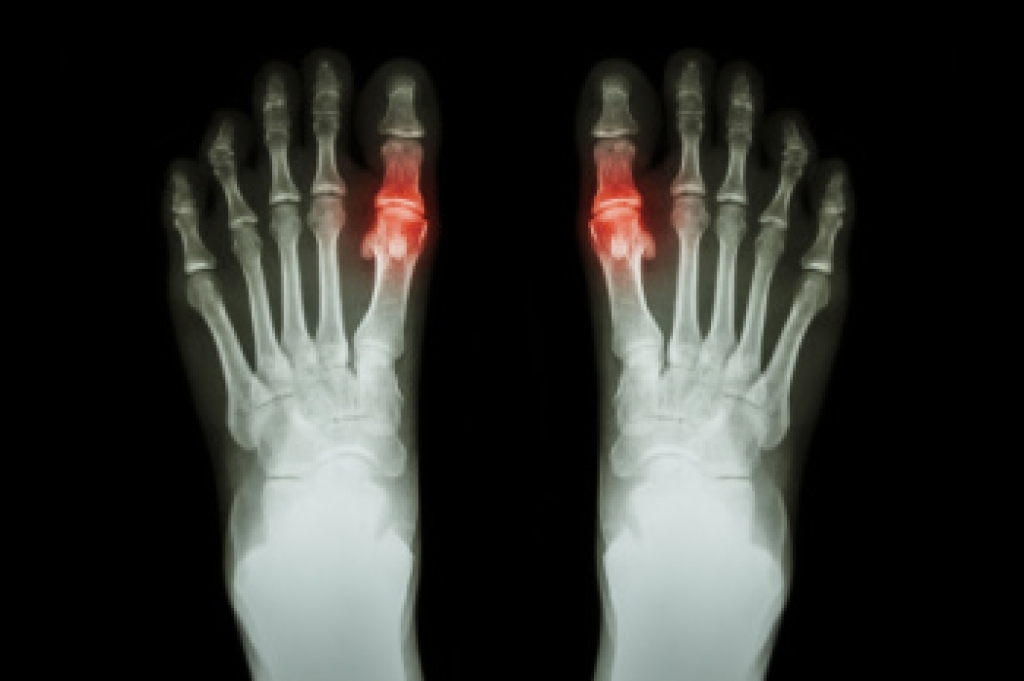

- Tarsal coalition, when there is an abnormal connection of two or more bones in the foot leading to severe, rigid flatfoot.